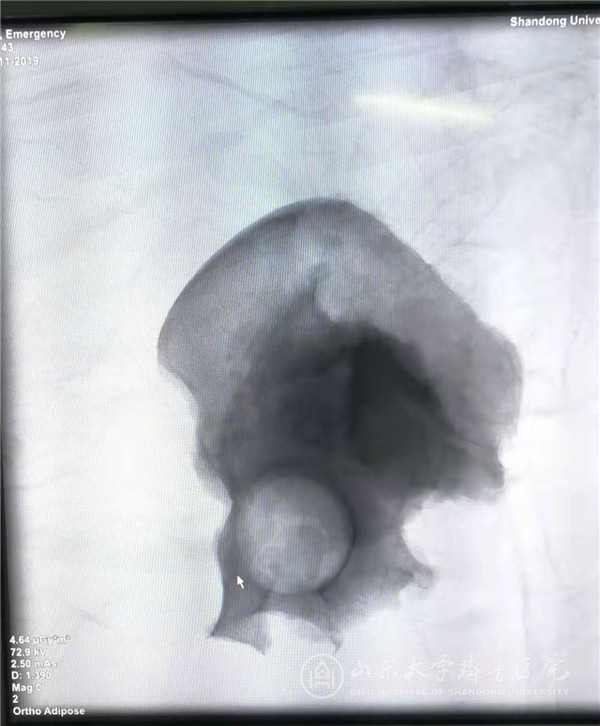

切除的左侧半骨盆透视影像